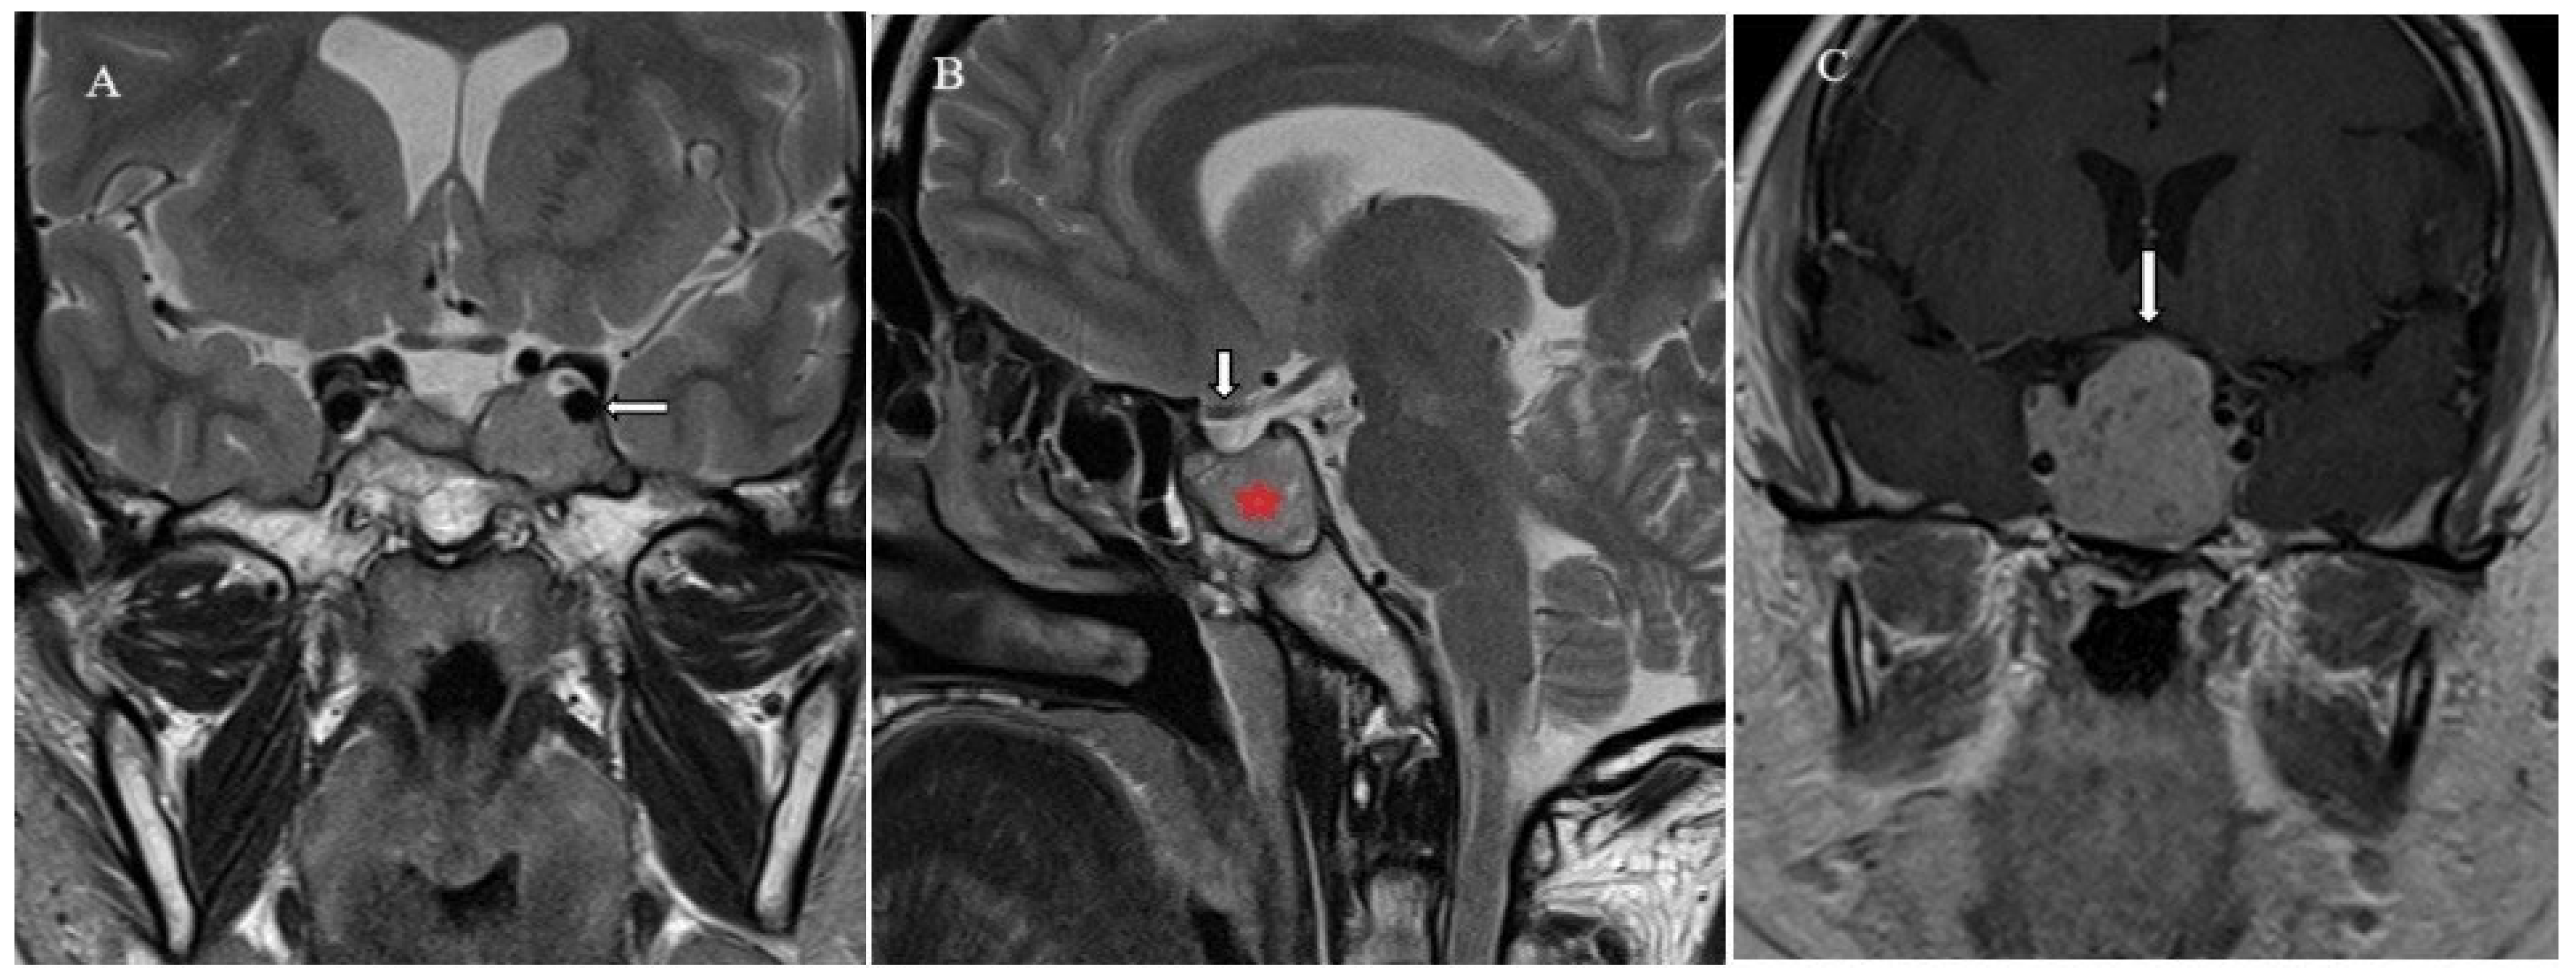

2.4. Brain Imaging